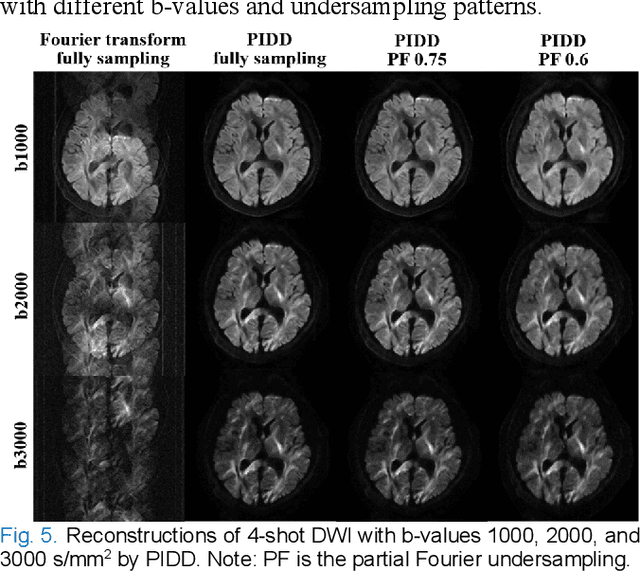

Abstract:In this work, we propose a Physics-Informed Deep Diffusion magnetic resonance imaging (DWI) reconstruction method (PIDD). PIDD contains two main components: The multi-shot DWI data synthesis and a deep learning reconstruction network. For data synthesis, we first mathematically analyze the motion during the multi-shot data acquisition and approach it by a simplified physical motion model. The motion model inspires a polynomial model for motion-induced phase synthesis. Then, lots of synthetic phases are combined with a few real data to generate a large amount of training data. For reconstruction network, we exploit the smoothness property of each shot image phase as learnable convolution kernels in the k-space and complementary sparsity in the image domain. Results on both synthetic and in vivo brain data show that, the proposed PIDD trained on synthetic data enables sub-second ultra-fast, high-quality, and robust reconstruction with different b-values and undersampling patterns.